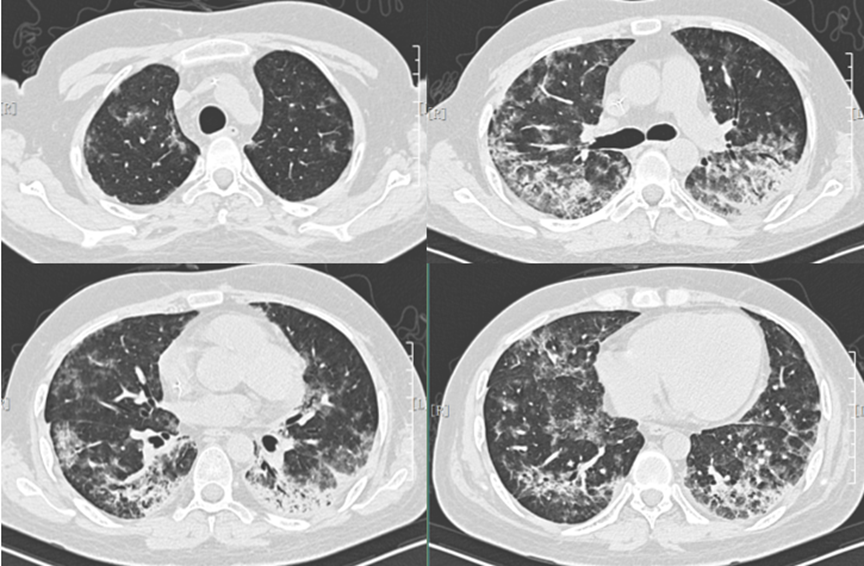

• 10月16日复查胸部CT示肺实质囊样变,间质增生及纵隔气肿(图5)

图片

图5  患者胸部CT(2018年10月16日)

• 10月24日复查胸部CT病灶逐步吸收,未见明显进展(图6)。精神、营养状况和肺功能好转,复查血常规基本正常,肝功能维持在轻度异常范围。肾功能正常。CRP及IL-6恢复正常,真菌D-葡聚糖降至122 pg/ml(↑)。

图6  患者胸部CT(2018年10月24日)